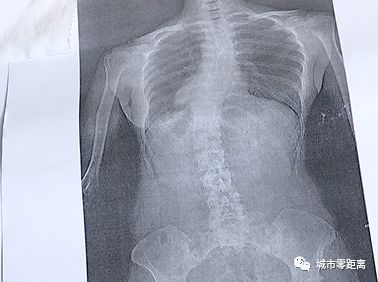

脊柱侧弯比较明显的特征是

驼背、高低肩或是长短脚等

经过医生初步判定,

零距离记者有轻微的脊柱侧弯的症状。